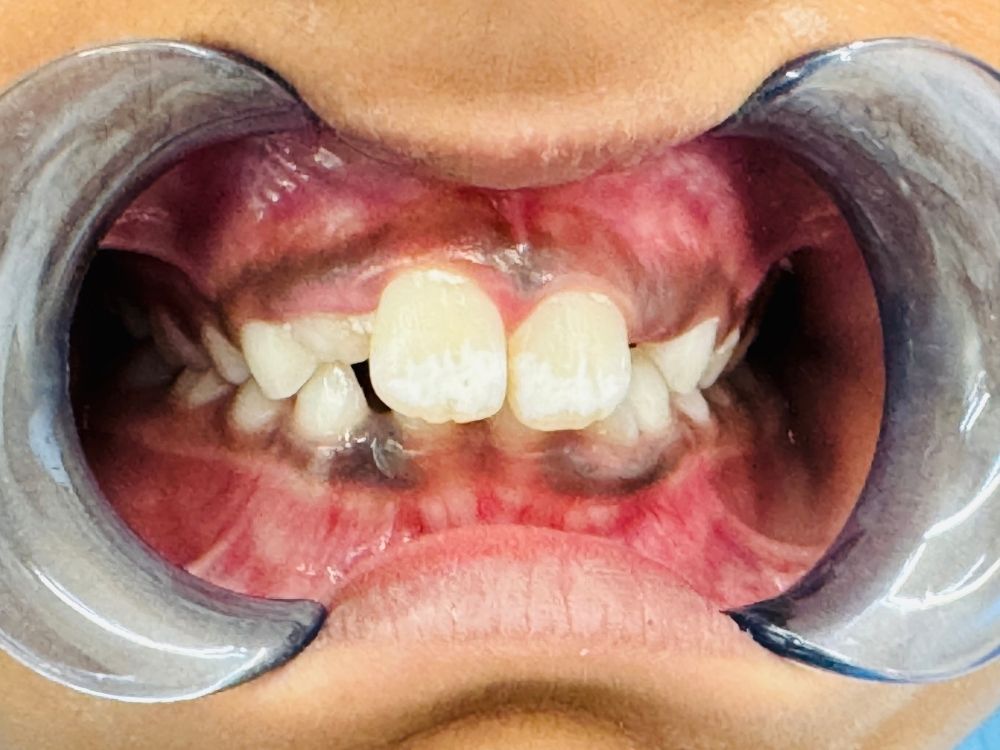

To keep your child’s teeth, gums, and jaw healthy, we recommend scheduling regular preventative care appointments. Children tend to eat high-sugar diets, which can be tough on their teeth. At their preventative care dental cleanings, we remove any plaque or tartar on their teeth and reduce their risk of gum disease. Additionally, we take the time to introduce them to our office and educate them on their dental health so that they know what they can do at home to take care of their smiles.

Regular cleanings help keep your child’s smile bright and cavity-free. If a cavity does occur, our gentle fillings restore the tooth’s strength and appearance. We also apply sealants to protect the grooves of your child’s molars — preventing decay before it starts.

First Visits & Patient Education Your child’s first dental visit is the foundation for a lifetime of healthy smiles. Our friendly team helps children feel comfortable while teaching them the importance of good oral hygiene in a fun and interactive way. We guide both parents and kids on brushing techniques, diet tips, and preventive care for strong, healthy teeth.